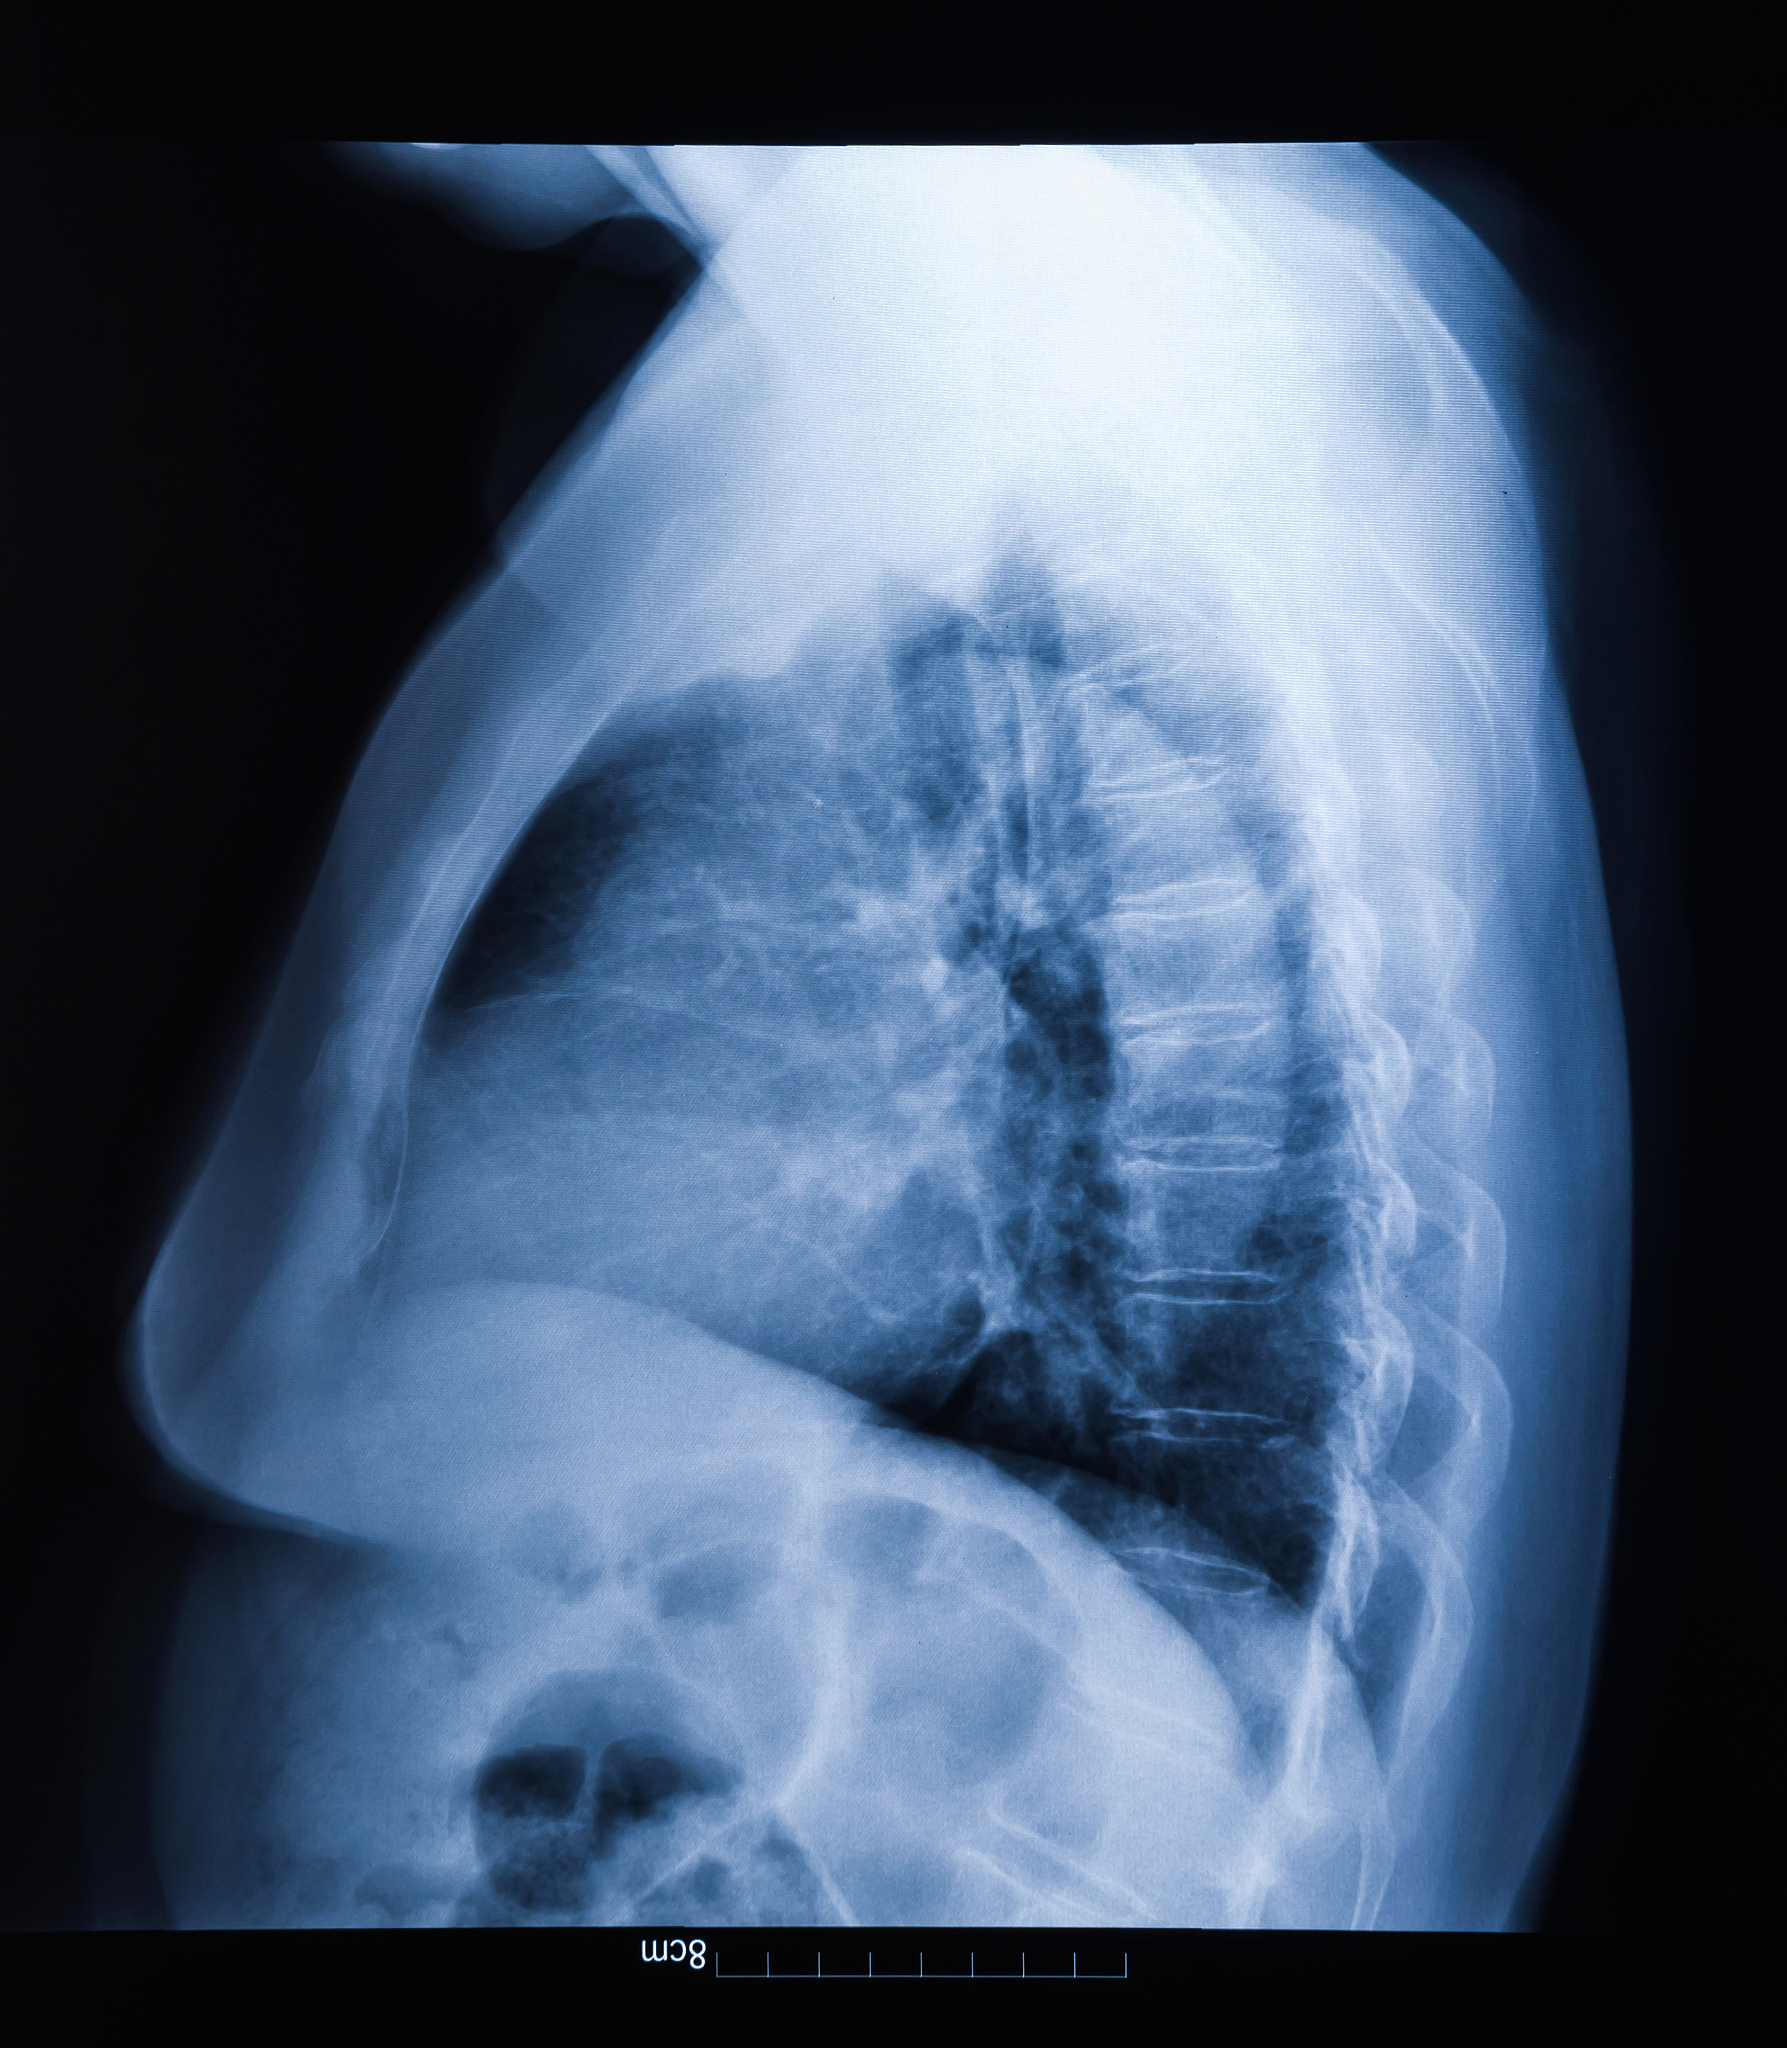

如果您不小心吃下电池,请立即寻求医疗帮助。医生可能会进行相关检查和治疗,如X光检查、内窥镜检查、手术等,以确保电池安全地从消化道中移除,并采取适当的措施来减轻任何潜在的损害。